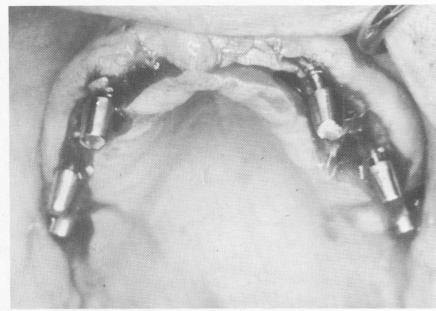

Fig. 11-151. The implants in place. Posteriorly, the double-posted implants were used for added retention of the pros-thesis.

4 Double posted implants for added retention of maxillary prosthesis